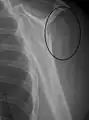

Types of major humerus fractures

Proximal

Proximal humerus fractures most often occur among elderly people with osteoporosis who fall on an outstretched arm.[9] Less frequently, proximal fractures occur from motor vehicle accidents, gunshots, and violent muscle contractions from an electric shock or seizure.[10][5] Other risk factors for proximal fractures include having a low bone mineral density, having impaired vision and balance, and tobacco smoking.[11] A stress fracture of the proximal and shaft regions can occur after an excessive amount of throwing, such as pitching in baseball.[6]

Definitive diagnosis of humerus fractures is typically made through radiographic imaging. For proximal fractures, X-rays can be taken from a scapular anteroposterior (AP) view, which takes an image of the front of the shoulder region from an angle, a scapular Y view, which takes an image of the back of the shoulder region from an angle, and an axillar lateral view, which has the patient lie on his or her back, lift the bottom half of the arm up to the side, and have an image taken of the axilla region underneath the shoulder.[9] Fractures of the humerus shaft are usually correctly identified with radiographic images taken from the AP and lateral viewpoints.[12] Damage to the radial nerve from a shaft fracture can be identified by an inability to bend the hand backwards or by decreased sensation in the back of the hand.[5] Images of the distal region are often of poor quality due to the patient being unable to extend the elbow because of pain. If a severe distal fracture is suspected, then a computed tomography (CT) scan can provide greater detail of the fracture. Nondisplaced distal fractures may not be directly visible; they may only be visible due to fat being displaced because of internal bleeding in the elbow.[7]